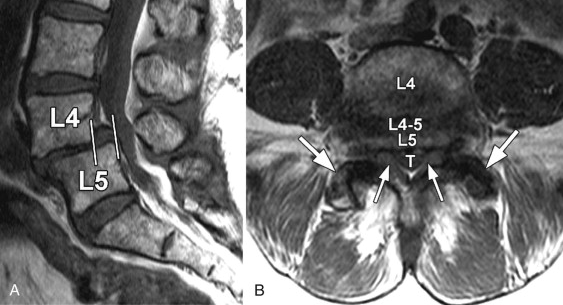

به چه تصویربرداری پزشکی نیاز دارم؟

- اشعه ایکس ستون فقرات به پزشک ستون فقرات کمک می کند تا ببینند آیا مهره در جای خود هست یا خیر.

- سی تی اسکن یا ام آر آی MRI ممکن است برای دیدن ستون فقرات با جزئیات بیشتر یا دیدن بافت نرم مانند دیسک ها و اعصاب لازم باشد.